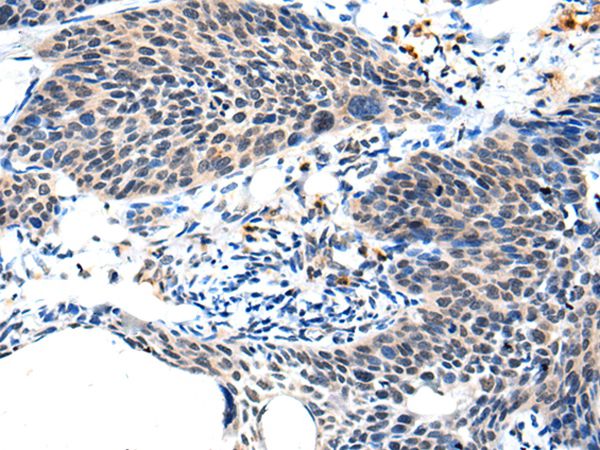

分类: 科研抗体货号: P43465别名: RN49018应用: IHC反应种属: Human